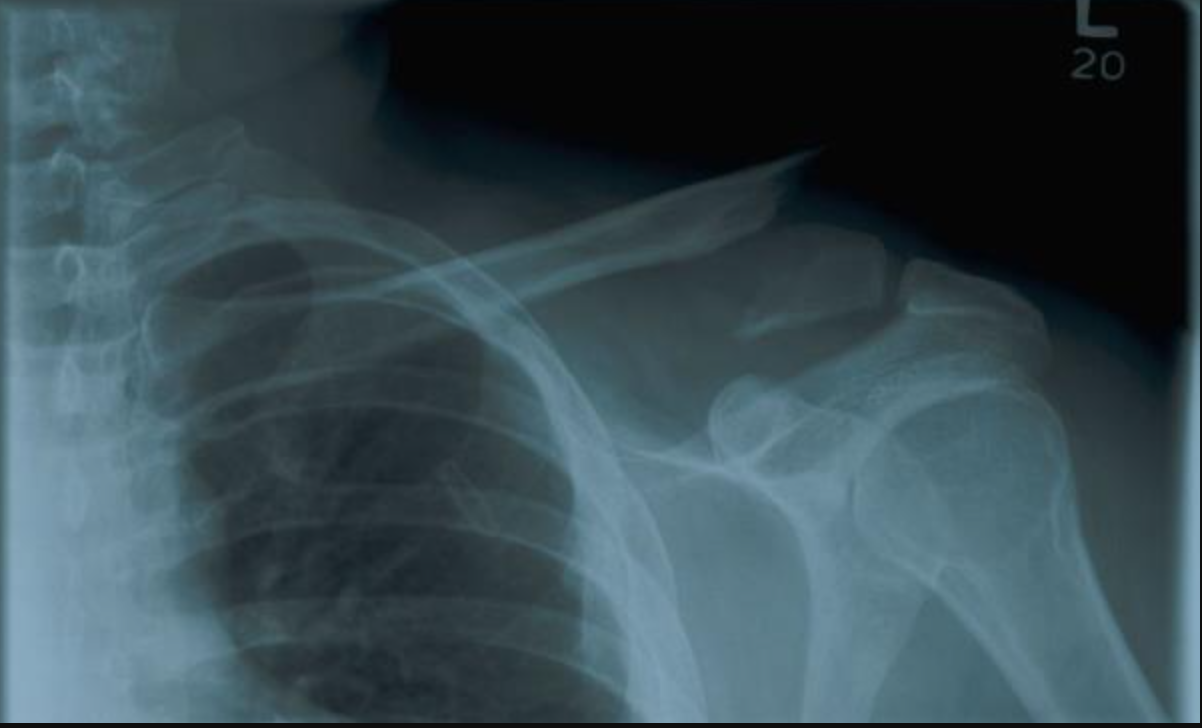

25 M with blunt force trauma from fall (3ft off a ladder onto his R shoulder)

Diagnosis?

Management?

A

Scapula fracture

Displaced fracture of the scapula lateral border

Fracture line passing through the scapula body

• Analgesia

• Immobilization in a sling for comfort and passive ROM exercises

• Pendulum sling usually 2-4 weeks

• Physical therapy

• F/U assessment if displacement

**Nondisplaced fractures of body, spine, acromion process do not require further therapy